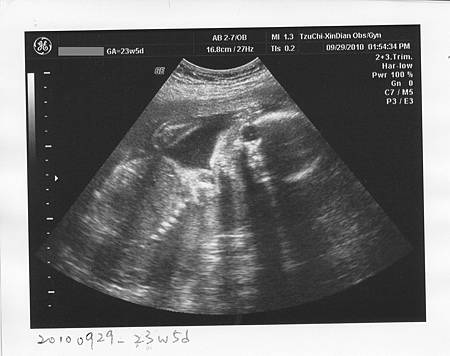

2010/9/29-23w5d

新店慈濟的楊濬光醫師真是太紅了

假日不說,連平日診都隨便上看100多號

常常要花很多時間等,但進去不到3分鐘,就被打發了

雖然阿光開朗親切,有問必答,寶寶正常也是好事

但等待的時間太長,看診時間又相對很短

對我們這兩個沒耐心的來說,實在沒辦法忍受

真是有禮貌的小孩,這麼小就知道要90度鞠躬啦~XD (醫生也說這個姿勢好有趣! )